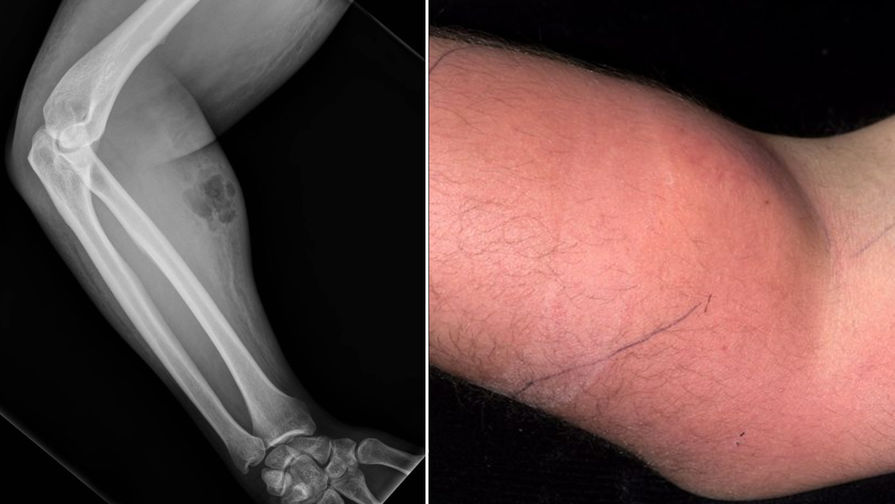

Мужчина обратился к врачам с жалобами на боль в спине. Она беспокоила его давно, но за три дня до обращения он переносил тяжелые предметы, и с тех пор боль только становилась сильнее. Осмотрев пациента, врачи обнаружили, что его правое предплечье опухло и воспалилось.

Такие эксперименты с собственным здоровьем привели к развитию бактериальной инфекции. Спустя 24 часа после последней инъекции она охватила все предплечье, вызвав отек и покраснение кожи. У мужчины не получалось ввести всю сперму в руку с одного раза, так что он сделал несколько проколов, которые и стали воротами для бактерий.

Рентгенограмма показала подкожную эмфизему — скопление воздуха в подкожной клетчатке. Анализ крови выявил повышенное содержание С-реактивного белка, маркера воспалительных реакций, до 150 мг/л при норме до 5 мг/л, что свидетельствовало об острой инфекции. Также вдвое были повышены лейкоциты. Врачи тут же ввели мужчине антибиотики.